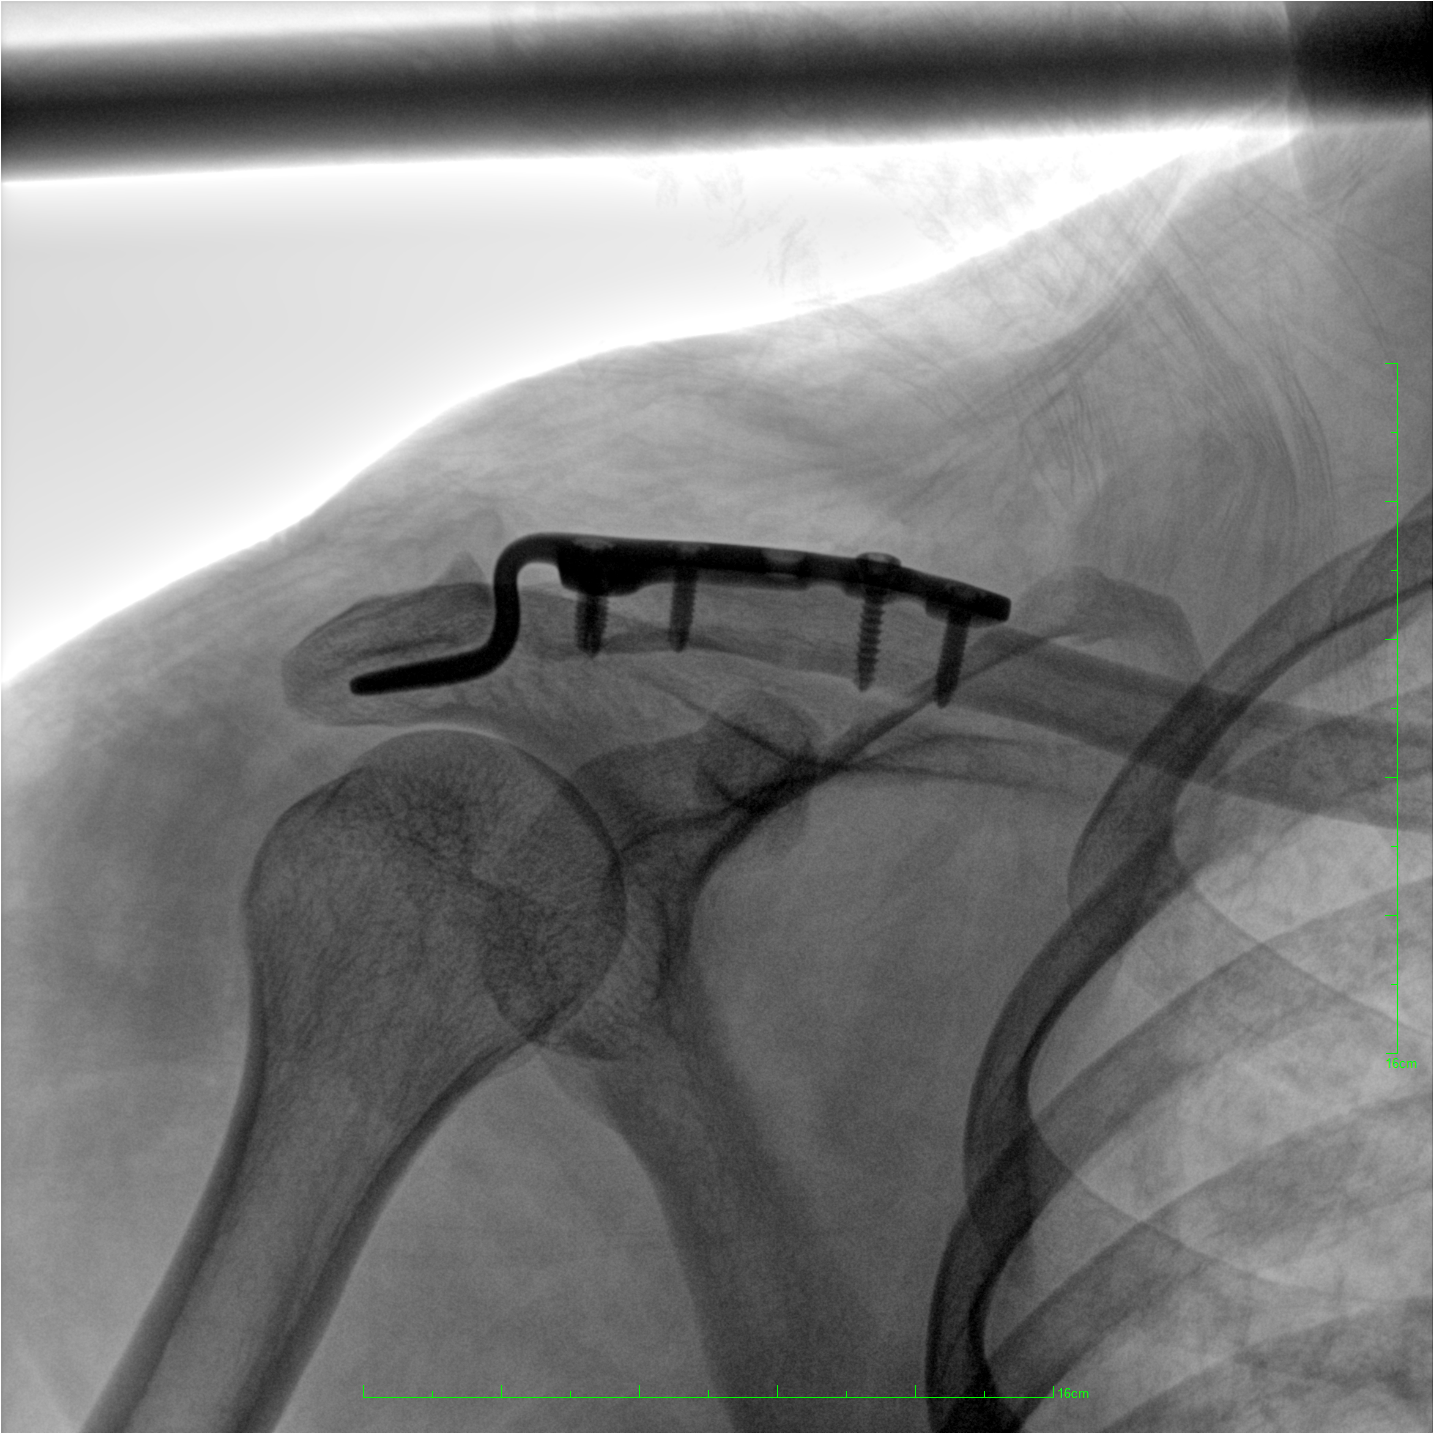

術(shù)中三維成像和橫斷面圖像提供多角度的手術(shù)診斷信息,輔助醫(yī)生進行術(shù)中評估判斷,諸如骨折復(fù)位情況和內(nèi)植入螺釘?shù)某叽绾臀恢?,輔助手術(shù)更好地完成。